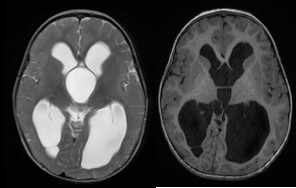

le kyste est développé dans un dédoublement de la membrane Liliequist, il soulève le plancher du V3 et se développe dans le 3ème ventricule, voire les ventricules latéraux.

c’est le meilleur exemple de kyste arachnoïdien avec mécanisme de clapet arachnoïdien qui trappe le LCS dans le kyste ; on le constate de visu lors de l’intervention endoscopique.

il entraîne donc une hydrocéphalie en principe obstructive ; en fait, il peut s’associer à une part d’hydrocéphalie dite communicante, et un certain nombre de patients ne sont donc pas guéris avec le seul traitement du kyste, ils nécessitent alors la pose d’une valve dans les suites.

elle est réalisée chaque fois que possible. le plus souvent il existe une dilatation ventriculaire qui donne accès au kyste. la fenestation endoscopique permet d’ouvrir le dôme du kyste, d’y pénétrer et d’ouvrir le fond du kyste dans les citernes de la base. Il s’agit donc d’une ventriculo-kysto-cisternostomie.

en post-opératoire, les ventricules restent dilatés, en général non sous pression

on objective la perméabilité des membranes du kyste et du plancher du 3ème ventricule. dans certains cas, une hydrocéphalie communicante peut se révéler secondairement.